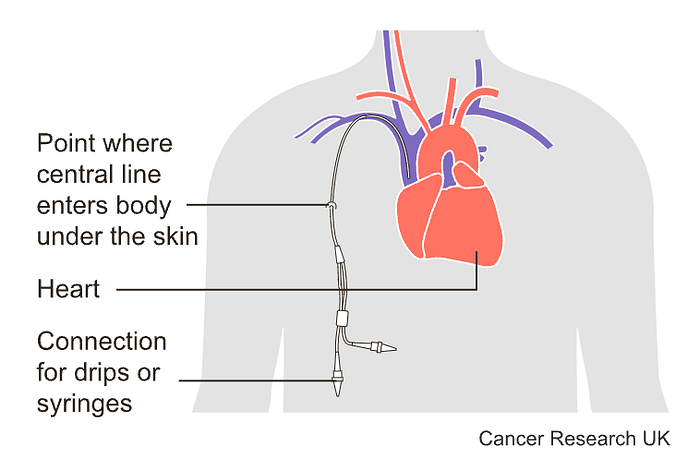

1) Intravenous chemotherapy

In this method, you can have treatment through a thin short tube (a cannula) that enters a vein in your arm each treatment session, or you might have treatment through a tunnelled central line. Long plastic tubes inject the drug into a large vein in your chest. A huge portion of the line remains in your body for months to be used to either extract blood or inject more treatment.

Sometimes problems may occur with tunneled central lines:

- You may get an infection.

- The line may get blocked.

- A blood clot can develop.

- The line may split, although rarely.